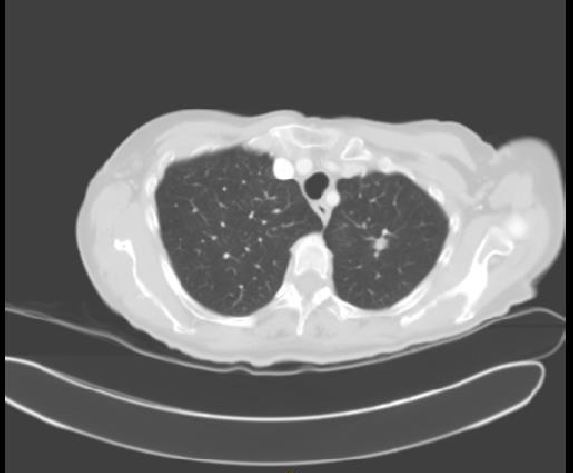

Figure 1.

This video shows a 73-year-old woman with a past history of gastric adenocarcinoma in 2007 and a recent small intraparenchymaal undiagnosed nodule in the left-upper lobe with radiological growth. The PET scan showed only a SUV max of 2.5 gr/mL image in the left-upper lobe. Bronchoscopy and transthoracic fine-needle aspiration (FNA) were negative for diagnosis. Lung function tests were normal.